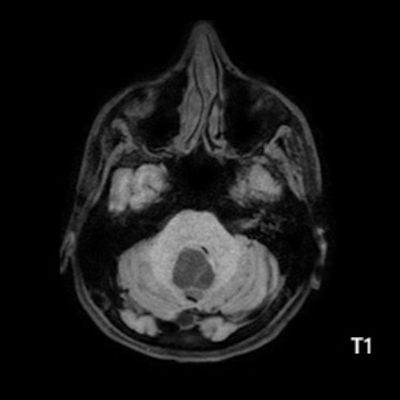

- B) Beyin MRG incelemesinde; 4. ventriküle bası etkisi oluşturan yaklaşık 3.5 cm boyutta, T2A hiperintens T1A hipointens kistik komponent (oklar) ve posteriorunda T1 ve T2A serilerde parankim ile izointens, içerisinde flow void alanların (oklar) izlendiği, post kontrast görüntülerde yoğun kontrast tutulumu gösteren mural nodül (oklar) barındıran düzgün sınırlı lezyon izlenmektedir.

- Kistik komponent: T1A hipointens, T2A hiperintens

- Mural nodül: T1A izo-hipointens, T2A orta derecede hiperintens olabilir.

- Kontrastlı incelemelerde mural nodül belirgin ve yoğun kontrast tutulumu gösterir. Ancak kist duvarında genellikle kontrastlanma beklenmez.

- T1 ve T2A görüntülerde flow voidler sıktır.